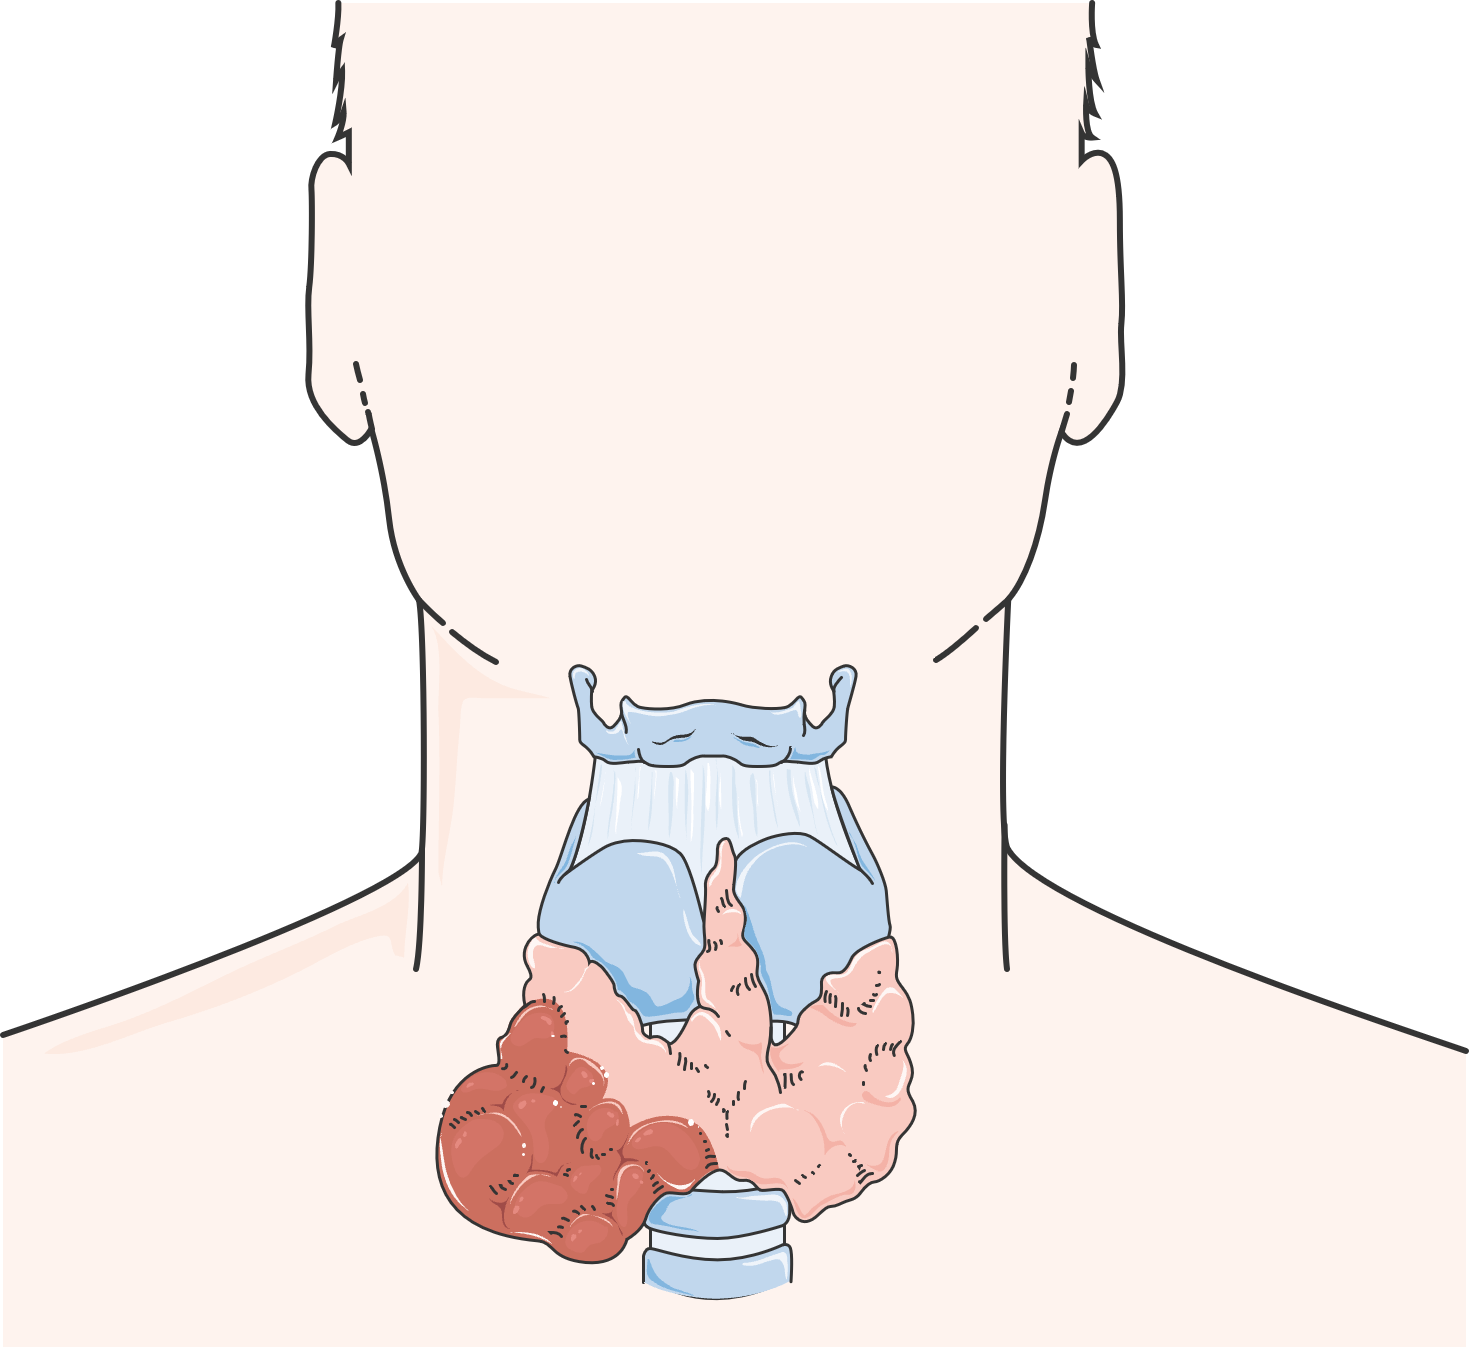

- Hepatomegaly, splenomegaly, lymphadenopathy — usually mild; bulky disease is uncommon

- Lymph node biopsy shows Castleman disease histology in 11–30% of cases

- Hypogonadism (most common) — erectile dysfunction, amenorrhea, gynecomastia

- Hypothyroidism

- Diabetes mellitus / glucose intolerance

- Adrenal insufficiency

- Hyperprolactinemia — newly identified as a risk factor for venous thrombosis

Note: Diabetes and thyroid abnormalities alone are excluded from minor diagnostic criteria due to high background prevalence.

- Hyperpigmentation (most common)

- Hypertrichosis (excessive hair growth)

- Skin thickening / scleroderma-like changes

- White nails (leukonychia)

- Digital clubbing

- Acrocyanosis

- Glomeruloid hemangiomas — highly specific for POEMS but rare

- Facial fat pad atrophy / facial lipoatrophy